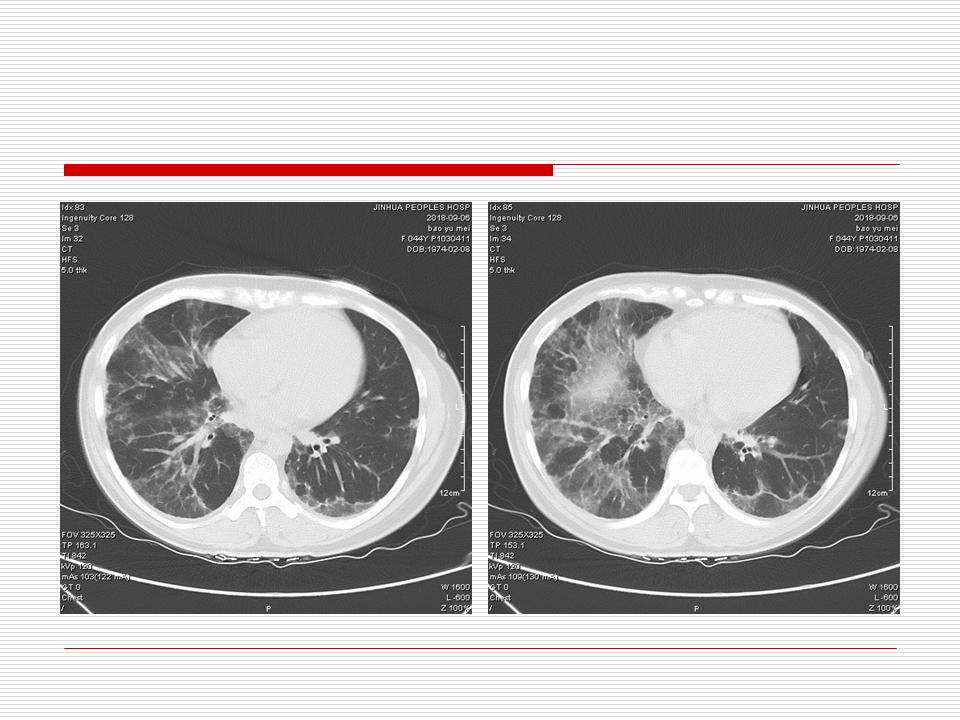

肺部阴影永恒且最重需要鉴别的是:到底是炎症还是肿瘤?但临床的病例中的影像表现难以界定或有些肿瘤特征,同时又有些炎症特点是非常常见的情况。作为临床医生我们怎么去总结分析,并找到之所以是炎症或之所以是肿瘤的细微差别或特点非常重要,也非常有用。2019.12.7浙江省2019年胸心外科学学术年会在宁波召开时,我的临床病例分析与经验总结<那些像肺癌的炎症与像炎症的肺癌>获得在大会交流的机会,以下为该PPT的内容,与你分享,希望对同道有益,有借鉴与启迪。若有探讨与进一不完善的建议,欢迎文末留言讨论: